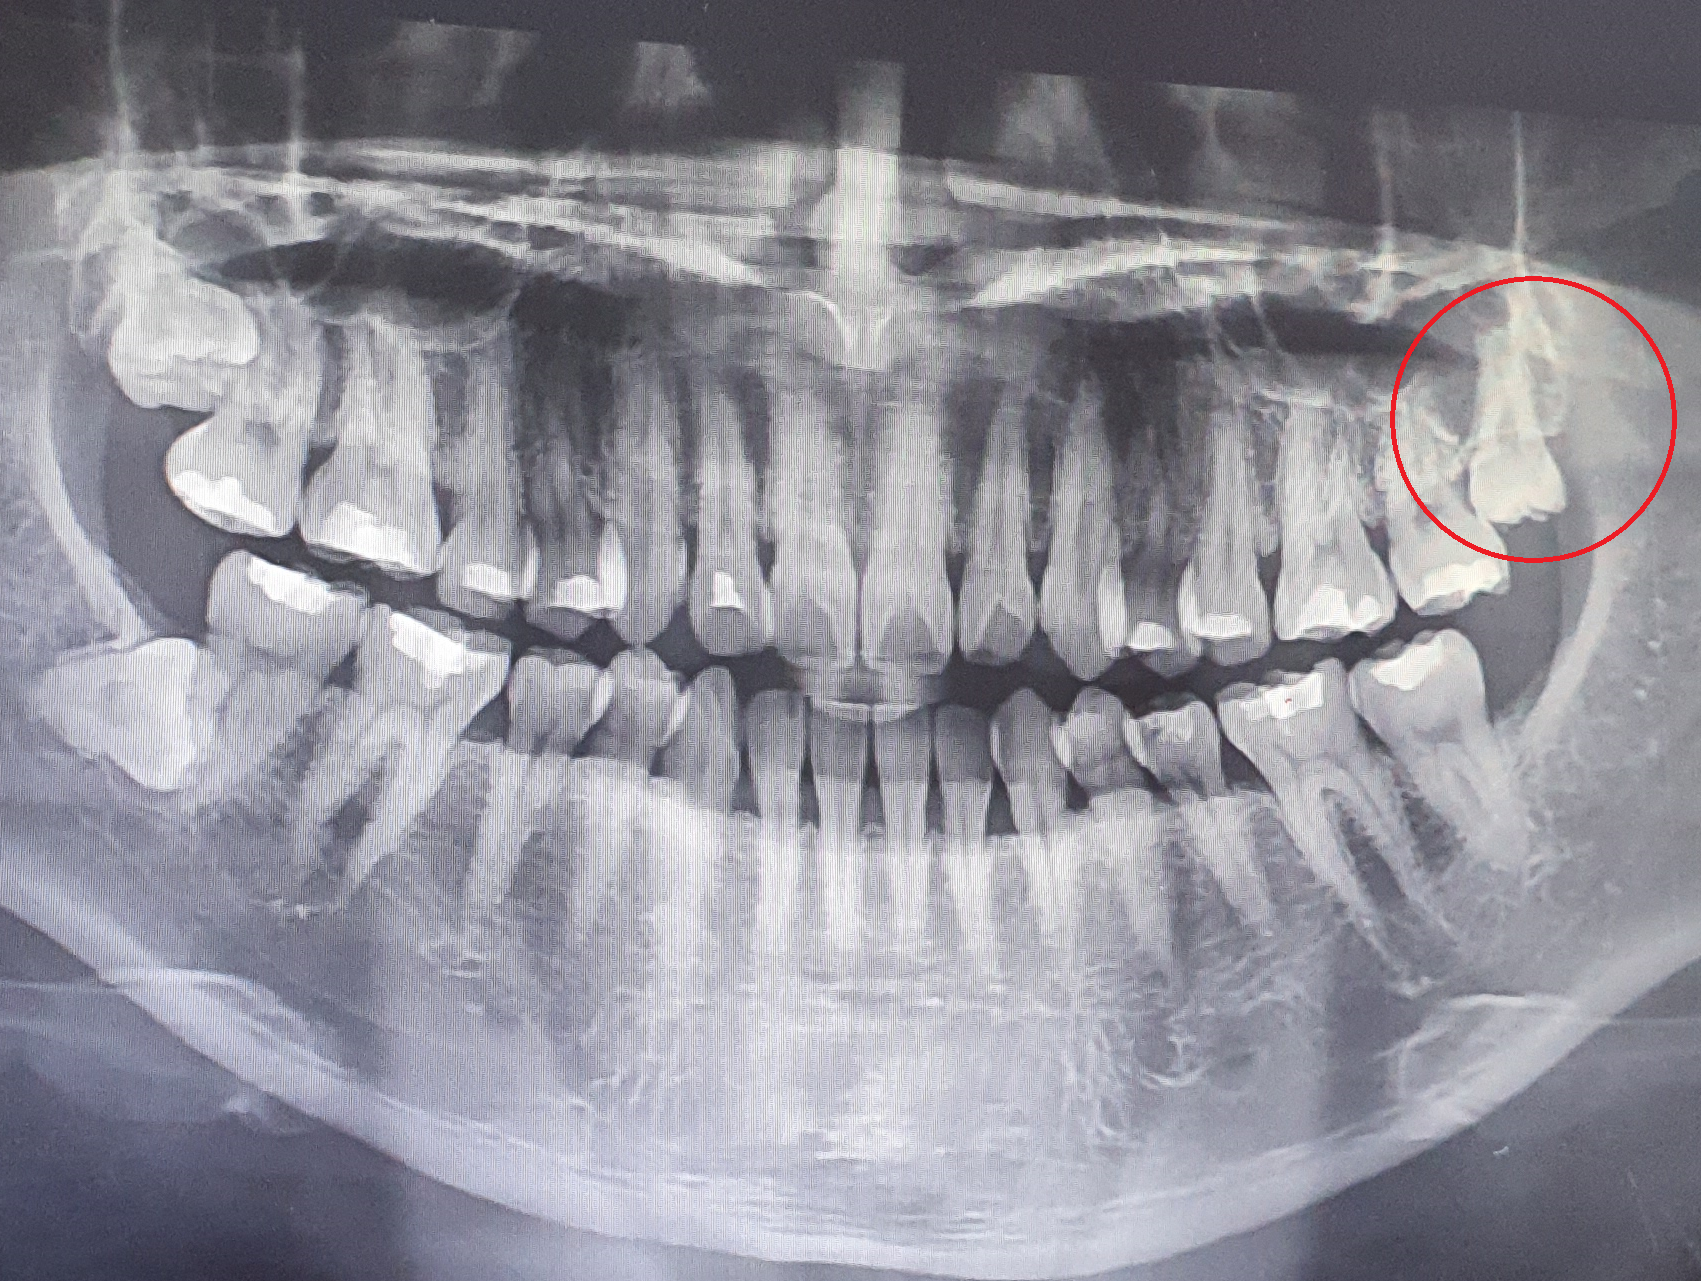

좌측 위에 사랑니가 반쯤 나와있었는데 그상태로 몇년이 흐르고 쓰는데 지장은 없었는데 치과 검진 중 사랑니 일부와 옆에 어금이가 썩어있었다. 그래서 치과 3군데를 가본 결과 빼는게 좋겠다고 해서 고민하다가 발치를 하였다. 두려웠지만 마취 후 생각보다 금방 발치했다. 5분도 안 걸린듯..

반대 쪽 위 아래에도 사랑니가 있는데 외관상으로 나오진 않았고 통증도 없었다. 저건 안나올거라고 해서 천만다행.. 근데 사랑니 자세가 굉장히 불안하다. 나중에 통증을 몰고 올 것 같은...

상악동이라는 빈 공간과 치아의 뿌리가 근접해서 발치시 뚫리는 뭐 그런 경우라고 하는데.. 발치할 때는 그런 경우가 생긴다는 말은 듣지 못했고 나 또한 그런 현상이 있는지도 몰랐었다.